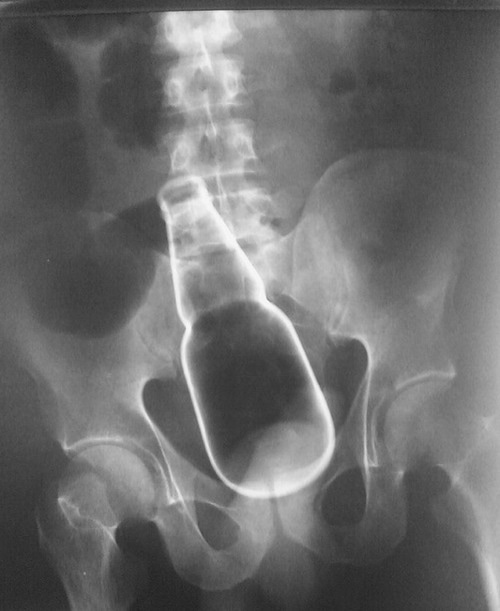

• 52122/04/18(月) 13:30:09

一応ビール瓶突っ込んだレントゲン貼っとく

• 53二次元好きの匿名さん22/04/18(月) 13:30:34

>>34

CT見て震えた

これよりでかい異物は多分無いと言われてもそりゃそうだろうという感想